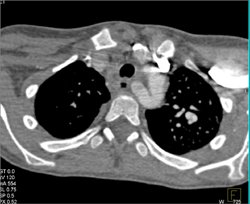

Diagnosis

Normal RCA